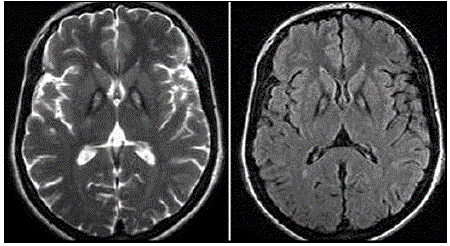

Paciente, sexo masculino, 29 anos de idade, apresenta quadro de parkinsonismo (ridigez em roda denteada e bradicinesia principalmente); distonia cervical; disartria e disfonia discretas; alteração comportamental com surtos psicóticos; retinopatia pigmentar; e, sinais de liberação piramidal ao exame físico neurológico. O quadro tem apresentado piora progressiva ao longo do tempo. Foi realizada a seguinte Ressonância de Crânio (RM de crânio); observe:

Enunciado 2606787-1

Assinale o provável diagnóstico desse paciente.